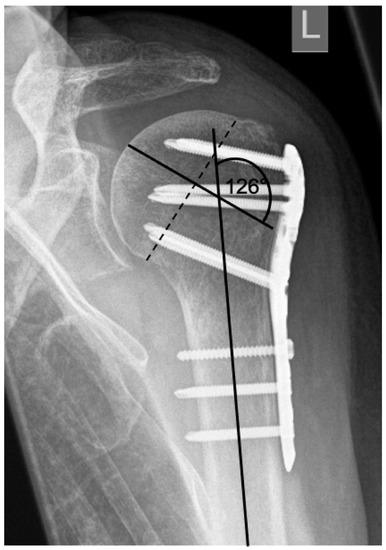

| Complication Type | Exemplary Images by X-rays or Pattern Images | Definition |

|---|---|---|

| 2c | ![]() | Type 2c is defined by a severe varus displacement (>20°) of the humeral head, which is associated with a screw cutout at the humeral head in parallel to Type 2a. In contrast to Type 2a, this varus displacement is characterized by an unstable osteosynthesis situation and progression. |